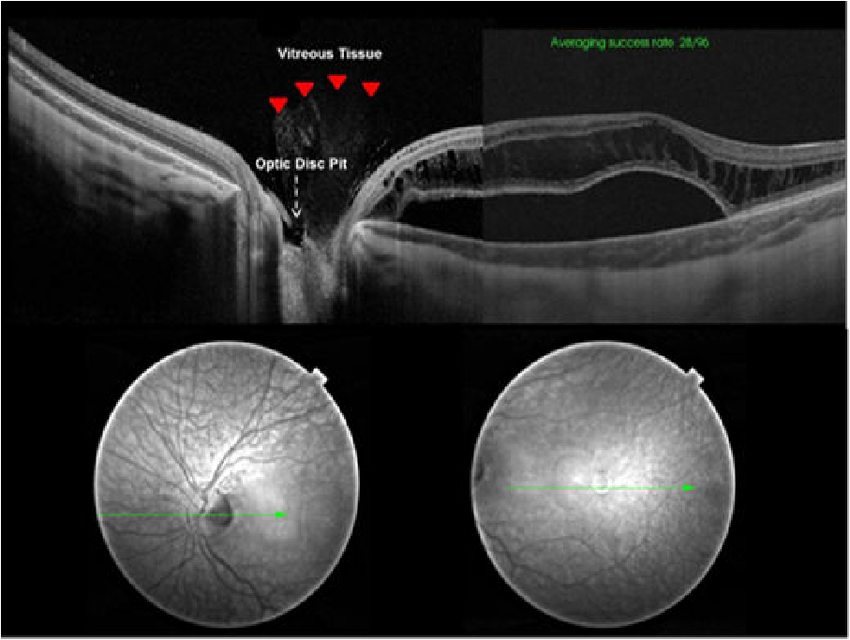

소아에서 선천적으로 발생하는 Congenital optic disc pit 에 비해서

어른에서 나이가들면서 발생하는것이기에, Acquired 라는 용어를 사용하며,

Pseudopit 이라는 용어 역시 Congenital optic disc pit에 비해서 다른 특징이 있기에 붙여진용어로, 이는 뒤에서 다시 설명하겠습니다.

<Congenital Optic disc pit 과의 차이>

Optic disc에 발생하는 구덩이 Pit 이 선천적으로 태어날때부터 가지는 경우가 있습니다.

약 1/10,000의 유병률을 가지며, 일측성으로 단안에서만 발생하는 경우가 80% 이상입니다.

이를 Congenital optic disc pit이라고하는데, 이는 실제로 disc 에 구멍이 나있고

그구멍이 시신경 주위를 둘러싸고 있는 뇌척수액(CSF)과 연결되어있습니다.

이로인해서 Pit 구멍을 통해 CSF leakage 가 발생하면서, 그 액들이 망막하 공간으로 고이면서,

망막박리, 망막하액으로 이어지는 경우가 약 40% 에 해당하는 경우입니다.

반면, APON 은 나이가들면서 발생하는 질환으로,

Congenital pit 과 대비하여, 사상판(laminar cribrosa)조직이 보일정도로 깊은 구덩이기는 하지만,

그 구덩이가 뇌척수액과는 연결되지 않습니다.

그래서 이러한 특징으로 인해, 망막하액이 동반되지는 않기에,

가짜구덩이라는 의미로, Pseudopit이라고도 합니다.